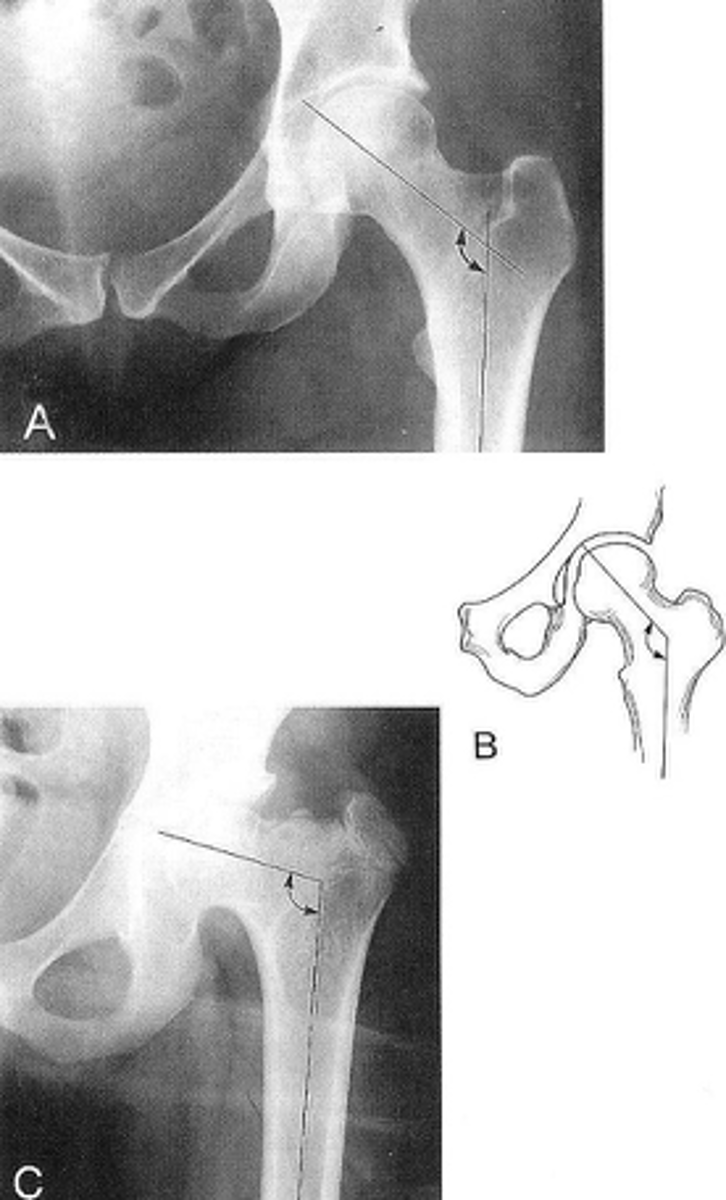

Femoral angle

ID measurement

<p>ID measurement</p>

- AP pelvis

- AP hip

What views are used to measure the femoral angle?

- Mid-axis of femoral shaft

- Mid-axis of femoral neck

- Intervening angle

Femoral angle landmarks

<p>Femoral angle landmarks</p>

120-130˚

Normal femoral angle measurement

<p>Normal femoral angle measurement</p>

Coxa vara

Femoral angle <120˚

<p>Femoral angle &lt;120˚</p>

Coxa valga

Femoral angle >130˚

<p>Femoral angle &gt;130˚</p>

Skinner's line

What views are used to see Skinner's line?

- Right angle tangent to tip of greater trochanter

Skinner's line landmarks

<p>Skinner's line landmarks</p>

Fovea capitis should lie above or at level of trochanteric line

Skinner's line normal measurement

<p>Skinner's line normal measurement</p>

Fracture or other causes of coxa vara

Clinical significance of Skinner's line

<p>Clinical significance of Skinner's line</p>

Klein's line

What views are used to see Klein's line?

Line along femoral neck

Klein's line landmarks

<p>Klein's line landmarks</p>

Line should intersect portion of femoral head

Klein's line normal measurement

<p>Klein's line normal measurement</p>

Slipped capital femoral epiphysis

Clinical significance of Klein's line

<p>Clinical significance of Klein's line</p>